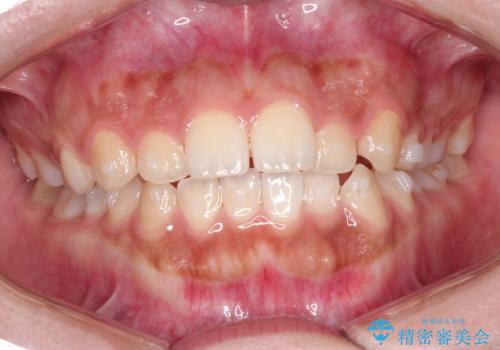

矯正治療で前歯の歯並びを整えてからセラミックほ装着する計画としました。

歯並びをかぶせ物のみで改善するのには限界があります。

矯正を併用することで、より審美的に良いかぶせ物を装着することが可能になります。